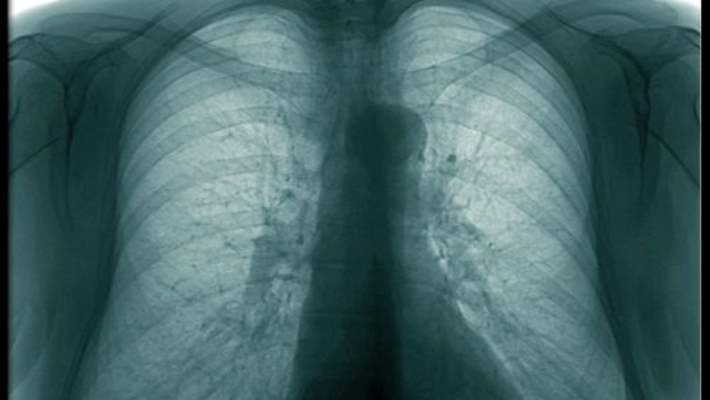

Akciğer Kanseri

Akciğer Kanserinin Türleri

Akciğer Kanseri Diğer Kanserlerden Daha Kötü Seyreder